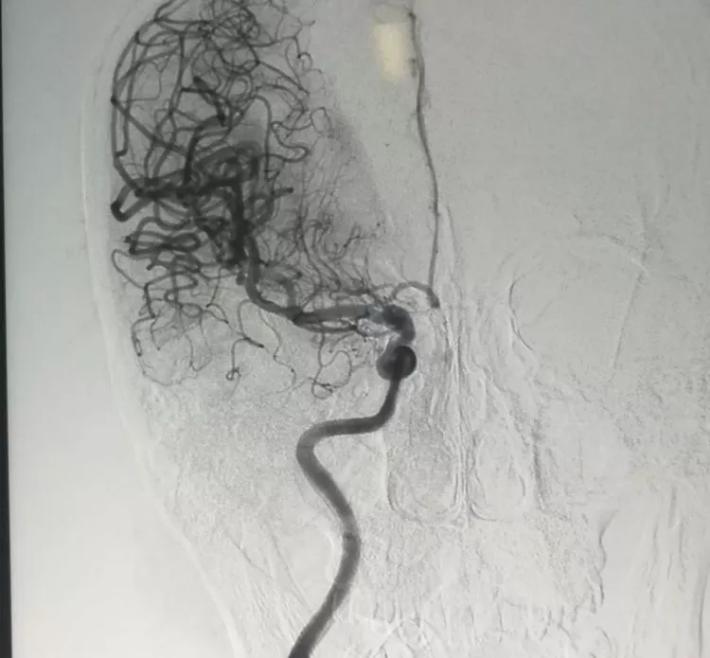

R-ICA正位:颈内动脉床突上段局部膨隆

R-ICA斜位:可见床突上段前壁一蘑菇状囊性突起,结合cT出血提示BBA,与家属沟通后选择介入治疗,我们拟采用Willis覆膜支架局部血管成形术!